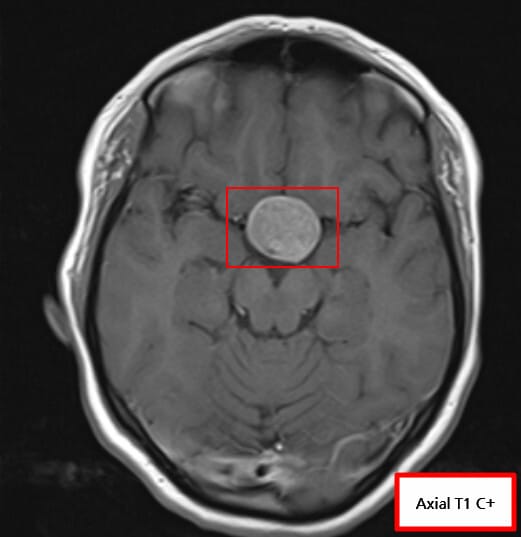

| 거대 선종(>10mm)에서 조영증강된 비균질 종괴로 나타나며, 주변 구조 압박 여부를 확인합니다. |

| ✅ 조영증강 MRI에서 불균질 조영 |

| 종양은 T1 조영에서 주변보다 낮은 조영도를 보이며 비균질한 양상입니다. |

| ✅ 해면정맥굴(Cavernous sinus) 침범 여부 확인 |

| 측방 침범 시 수술 접근과 예후에 영향을 미칩니다. |